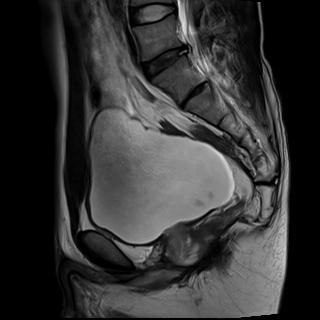

上圖為首發(fā)直腸癌患者,并有睪丸鞘膜積液。